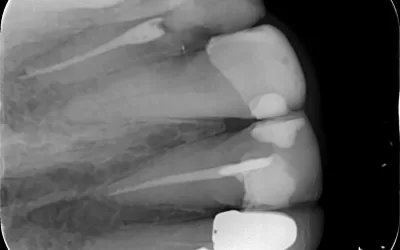

بارداری به دلیل تغییرات هورمونی میتواند سلامت دهان و دندان را تحت تأثیر قرار دهد. التهاب لثه، پوسیدگیهای پیشرفته و حتی عفونت دندانی در این دوران شایعتر است. در شرایطی مثل نیاز به عصبکشی دندان یا حتی کشیدن دندان، گرفتن عکس دندان برای تعیین عمق پوسیدگی یا بررسی وضعیت ریشه ضروری است. اگر این عفونتها درمان نشوند، میتوانند برای سلامت مادر و جنین خطرناکتر از خود عکسبرداری باشند.

اشعهای که در رادیوگرافی دندان استفاده میشود بسیار کم است و به طور مستقیم به جنین نمیرسد. استفاده از دستگاههای دیجیتال امروزی، میزان اشعه را به حداقل میرساند. همچنین در کلینیکهایی مثل کلینیک دندانپزشکی زاگرس، از پیشبند سربی مخصوص برای محافظت از شکم و تیروئید استفاده میشود تا هیچ نگرانی برای مادر وجود نداشته باشد. در نتیجه، اگر نیاز به درمان فوری باشد، عکسبرداری دندان بیخطر محسوب میشود.

بر اساس مطالعات، میزان اشعه رادیوگرافی دندان بسیار کمتر از آستانهای است که میتواند به جنین آسیب برساند. به همین دلیل، اگر همه موارد احتیاطی رعایت شود، عکسبرداری دندان در بارداری خطری ندارد. در واقع، عفونتهای درماننشده دندانی، تهدید جدیتری برای سلامت جنین نسبت به اشعه ایکس محسوب میشوند.